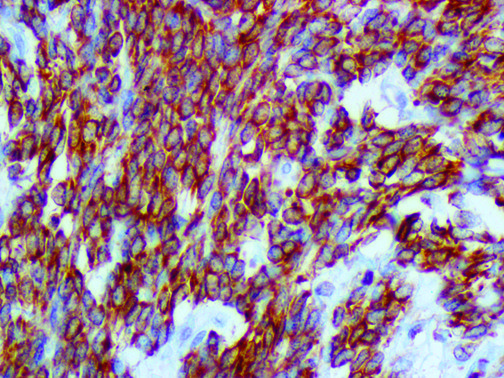

The first cytokines released are interleukin 1β (IL-1β) and tumor necrosis factor-α (TNF-α), which attract a variety of circulating white blood cells (WBCs) to the infection site, including neutrophils, monocytes, macrophages, and natural killer (NK) cells. This response, along with the antipathogenic chemicals released by these cells (i.e., complement), comprise the innate immune response. These cells directly attack the invading pathogen and also release additional cytokines, chief among them interleukin-1 and 6 (IL-6). IL-6 is essential for invoking the adaptive immune response, which calls T-cells, B-cells, and T helper (Th) cells to the infection site. IL-6 also stimulates further recruitment, proliferation and activation of macrophages.

This activation induces inflammatory monocytes to highly express IL-6, starting a localized and then systemic cascade effect that results in hyperproduction of IL-6, which accelerates the inflammatory process. Because IL-6 also increases vascular permeability, excessive levels cause blood vessels to become very leaky. This, along with clotting factors released from vascular endothelial cells, stimulates the coagulation cascade, resulting in microthrombosis (tiny clots), which leads to ischemia and tissue death of the kidney, intestines, heart, liver, brain and extremities.